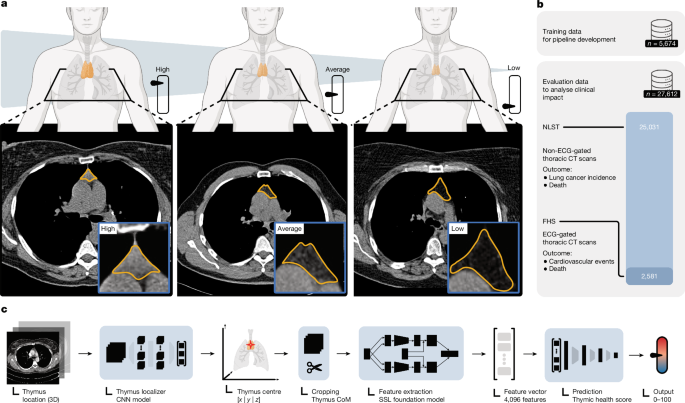

Thymus health is a predictor of lifelong well-being and immunotherapy effectiveness

Nature, Published online: 18 March 2026; doi:10.1038/d41586-026-00633-6It was thought that the thymus serves its purpose for the immune system early in life....

Thymic health and immunotherapy outcomes in patients with cancer - Nature

Nature, Published online: 18 March 2026; doi:10.1038/s41586-026-10243-xA deep-learning approach applied to routine CT scans is used to quantify the health of...

Thymic health consequences in adults - Nature

Nature, Published online: 18 March 2026; doi:10.1038/s41586-026-10242-yAssessing thymic function and health has highlighted the lifelong importance of the th...